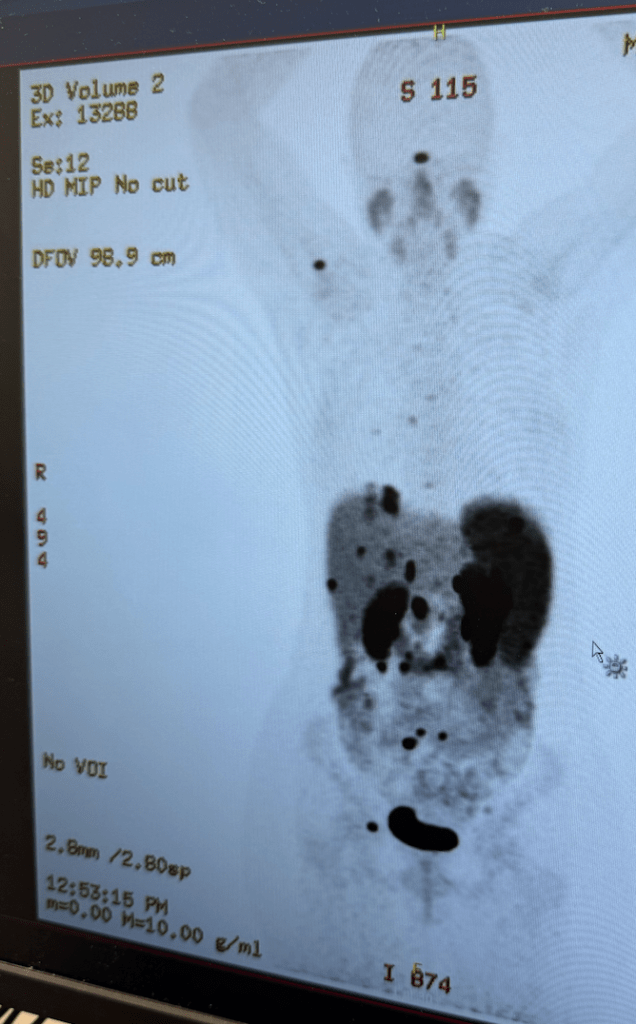

On Tuesday I had a 64Cu DOTATATE PET scan. This is only my second time having this particular scan, and last time in 2022 it revealed that my cancer had metastasized in a big way, which completely blindsided me. This time around I am much more mentally prepared to hear “bad news”: I belong to two support groups, I go to therapy every other week, and now I know I’m strong-willed and tough enough to heal after a brutal surgery!

It is indeed “bad news”. My disease has progressed in spite of my monthly Lanreotide shots. Numerous tumors can be seen in my liver, lymph nodes, spleen, abdominal cavity, and right breast.